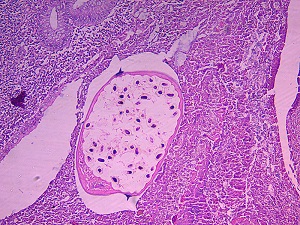

An 18-year-old male living in India presented with recurrent periumbilical abdominal pain for one week. Other symptoms included mild anemia and eosinophilic leukocytosis. The patient underwent an appendectomy and the appendix was sent to pathology. Sections were obtained, stained with hematoxylin and eosin (H & E) and reviewed. A worm was discovered in the lumen of the appendix and Figure A shows a low magnification view of a cross-section of the worm in the lumen. Figure B shows a higher magnification of the cross-section and Figure C highlights ova observed in utero. What is your diagnosis? Based on what features?

Figure A